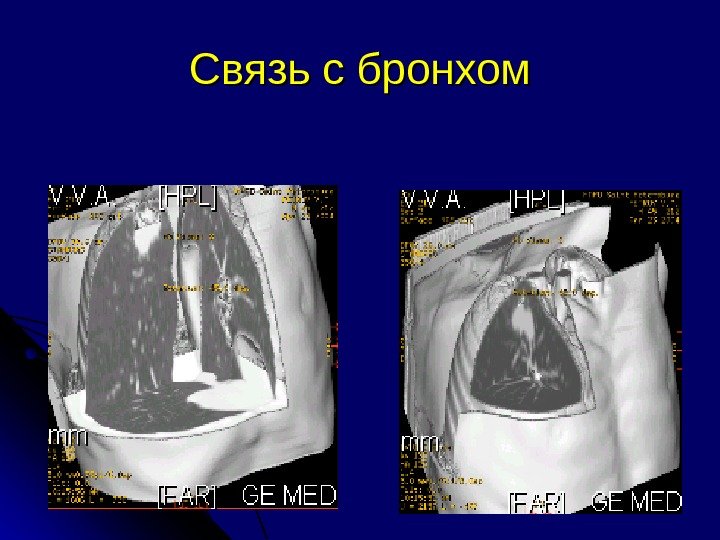

Связь СОЛ с бронхом В стенке бронха Бронх входит в узел • Раздвигает бронхи карцинома добро Если нет связи с бронхом необходима пункция

Связь с бронхом